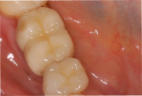

Mikrochirurgischer Wundverschluss

Gingivatransplantat fixiert

Zustand 3 Wochen post OP